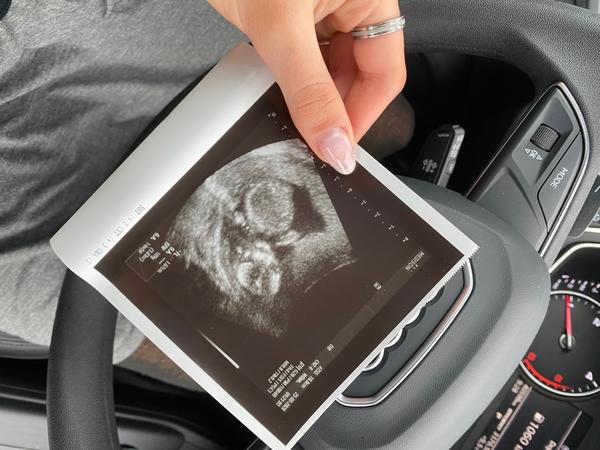

Holka nebo kluk😁. Co myslíte?

Ahoj holky dneska jsem 14 tt..na prvním screeningu jsem byla tento týden pan doktor řekl, že to vypadá na kluka když jsme se zeptali, chtěla bych se zeptat ještě vás co si myslíte jestli opravdu kluk? nebo to tam spíš nevidíte a myslíte si holčičku.? 😁 vím že fotka je taková dost na nic na určení pohlaví, ale jen pro zajímavost chci vědět co tam vidíte vy?😊 děkuji

Ahoj holky chtěla jsem se zeptat jestli tady vidíte co by to mohlo byt na 1. screeningu 14tt. Nechala jsem si záznam nahrát na flashku a díky tomu objevila hned na začátku tenhle záběr jinak po celou dobu potom už nic nešlo doktorce najít prcek sebou hrožně Šil. Mě přijde, že holka protože to má tak nějak rovně s páteří s nebo vám přijde, že by to měl být kluk, že to má spíše nahoru ? Děkuji za případné odpovědi. Na další screeningu jdu až v lednu a to už se z toho asi do té doby zblázním. Za dva týdny jdu teda ještě k mému gyn. Takže budu 16+3tt ale ten i u prvního řešil jiné věci než pohlaví tak nevím jestli mi to teď bude hledat.

@gympl no malý byl špatně natočený a když jsem řekla dr jestli by mi neřekla pohlaví tak mi řekla no v 14+6tt asi těžko..🙄 tak jsem jí řekla, že na screeningu nám řekli už chlapečka a celkově byla totálně nepříjemná dneska asi kvůli tomu, že měla celkem plnou čekárnu nebo nevím..tak jsem se rozhodla, že se objednám na 3d utz + normální utz protože další kontrola až za 4 týdny a tak dlouho se mi čekat nechce 🙃😊 takže mě akorát dneska Dr vytocila..🙄 takže mám takovou pitomou foto a malý vypadá jak mimozemšťan 😂